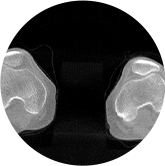

• 髋关节

• 膝关节

FOV最大350mm

支持双腿或双侧髋关节扫描 | 方便对比,降低漏诊误诊

FOV 250mm

FOV 350mm